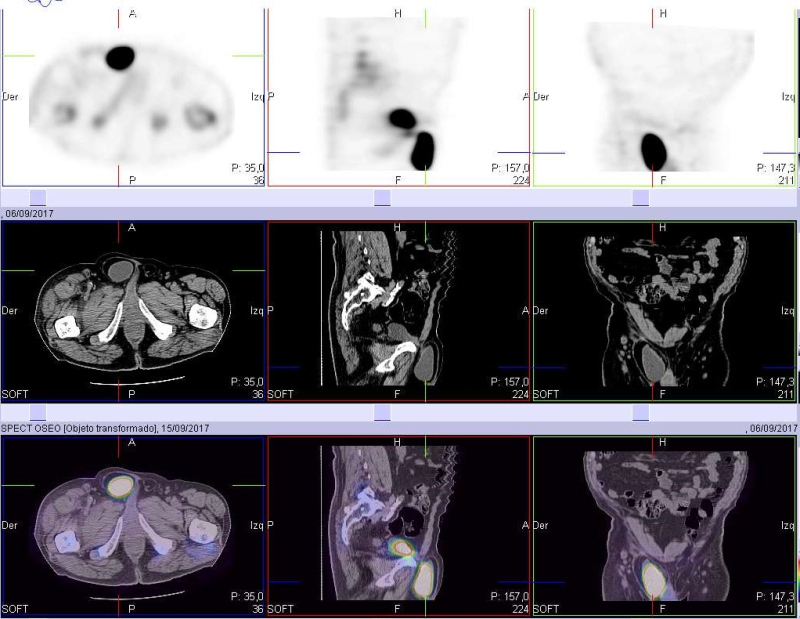

Se presenta el caso de un paciente masculino de 70 años con un único antecedente de carcinoma basocelular invasivo previamente operado, al cual le es solicitado un centellograma óseo debido a una lesión en alerón ilíaco derecho reportada en una tomografía computarizada (TC) de pelvis. Se realiza rastreo de cuerpo completo con 99mTc-MDP, imágenes estáticas de pelvis y SPECT. En el estudio de cuerpo completo se observó lesión en cresta ilíaca derecha, hipercaptante con componente lítico central, junto con un foco de hipercaptación de intensidad similar a la vejiga, proyectado por debajo de la rama superior del pubis derecho, de aspecto sacular (fig. 1). En las imágenes segmentarias con vistas anteroposteriores y laterales se evidencia que el hallazgo es de ubicación anterior respecto a la rama isquiopubiana derecha (fig. 2). En el estudio SPECT se confirma una gran lesión hipermetabólica con área central fotopénica de aspecto redondeado, que protruye de la cresta iliaca derecha y no respeta bordes anatómicos. Además, se evidencia claramente la existencia de conexión entre la vejiga y la zona hipercaptante de aspecto sacular ya mencionada (figs. 3 y 4).

Por estar disponible la TC de pelvis previamente realizada, se procedió a fusionar las imágenes (figs. 5 y 6) en las cuales se verifica conexión de la vejiga con una hernia inguinal (que no fue reportada en la TC) y la conocida lesión lítica en ala ilíaca derecha, con componente de partes blandas que se extiende al músculo ilíaco engrosado, sin reacción perióstica, característica de secundarismo. En una nueva TC en busca de la neoplasia primaria, se identifica una tumoración sólida en lóbulo superior del pulmón derecho, de aproximadamente 57 x 44 mm (fig. 7), sugestiva de carcinoma broncopulmonar (CBP).